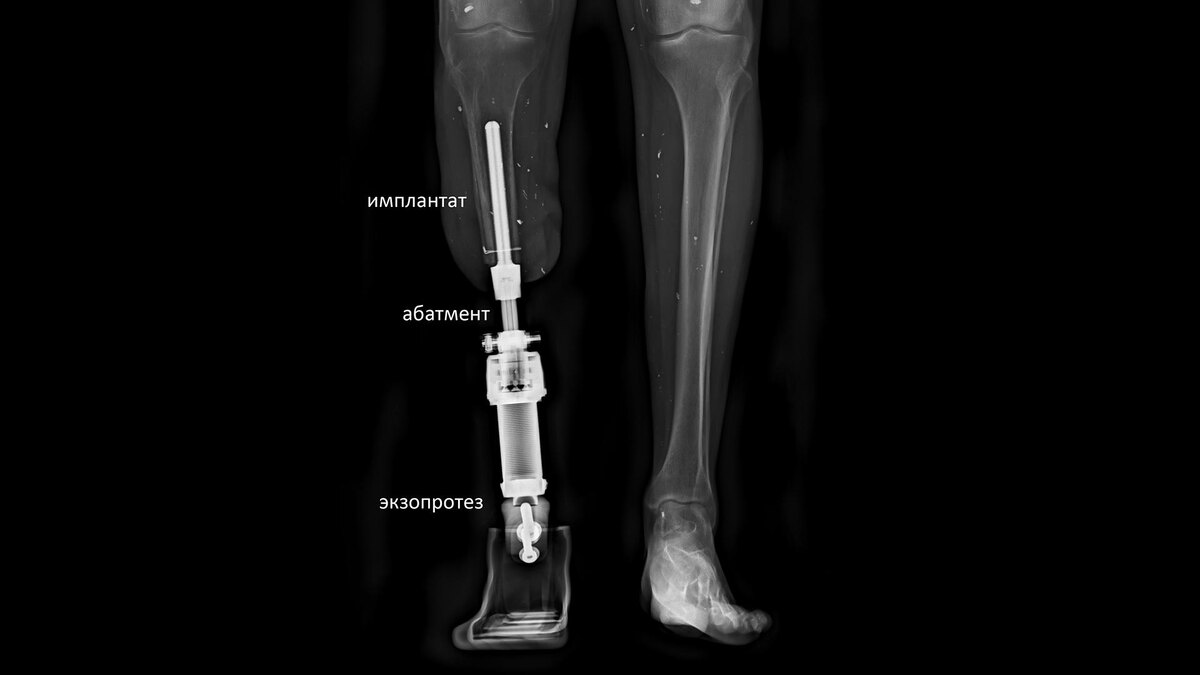

Остеоинтеграционный протез представляет собой систему из трёх основных элементов:

• Имплантат: Титановый стержень, изготовленный по индивидуальным меркам, который вживляется в кость культи и срастается с ней (остеоинтеграция).

• Абатмент: Переходник, соединяющий имплантат внутри тела с внешней частью протеза. Он проходит сквозь кожу и служит опорой для крепления протеза.

• Экзопротез: Современный внешний модуль, который крепится к абатменту и заменяет утраченную конечность.